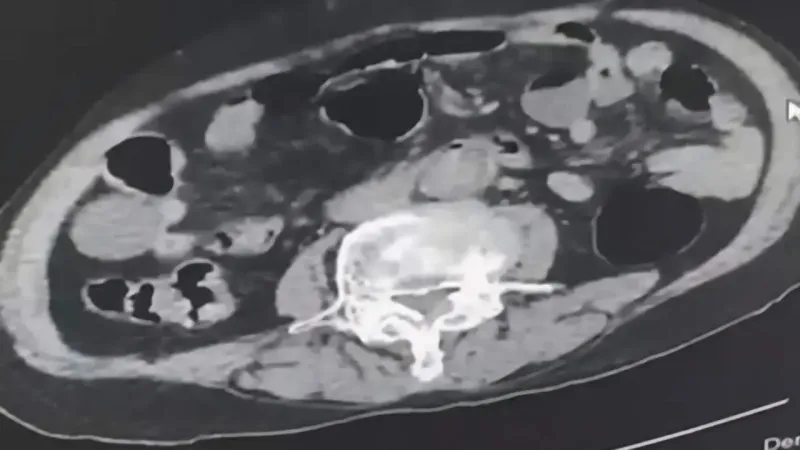

Şüpheliler üzerinde ve adreslerinde yapılan aramalarda, 6 parça halinde toplam 145 gram metamfetamin ile 260 gram sıvı halde sentetik ecza maddesi ele geçirildi. Yapılan incelemede yabancı uyruklu şüphelilerden birinin uyuşturucu maddeyi cinsel organında sakladığı ortaya çıktı.